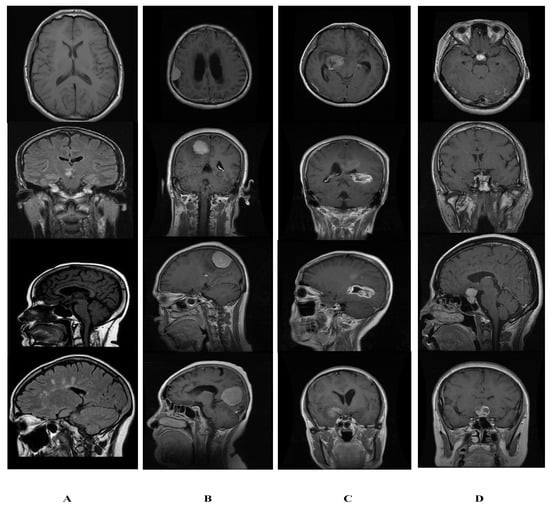

We collect a brain tumor data set of normal and tumor images; normal images are collected from the open-source Kaggle website [40] and named as dataset1 (DS-1). Furthermore, tumor images are taken from a publicly available CE-MRI figshare [19], titled dataset2 (DS-2). We collected 5058 images containing 1994 healthy patients and 3064 tumor images; thus, the acquired dataset is imbalanced and called dataset3 (DS-3). In the phase 01, detection is performed on DS-3, which contains (5058) MR images, 3064 of which are tumor images, and 1994 of which are normal brain MR images. The classification stage categorizes tumor instances (3064) brain tumor MR images into different family classes, i.e., glioma, meningioma, and pituitary by using DS-2. Sample images of normal brain and tumors are shown in Figure 5.

Figure 5.

Sample image from dataset of normal and tumor images. (A) Normal. (B) Glioma. (C) Meningioma. (D) Pituitary.